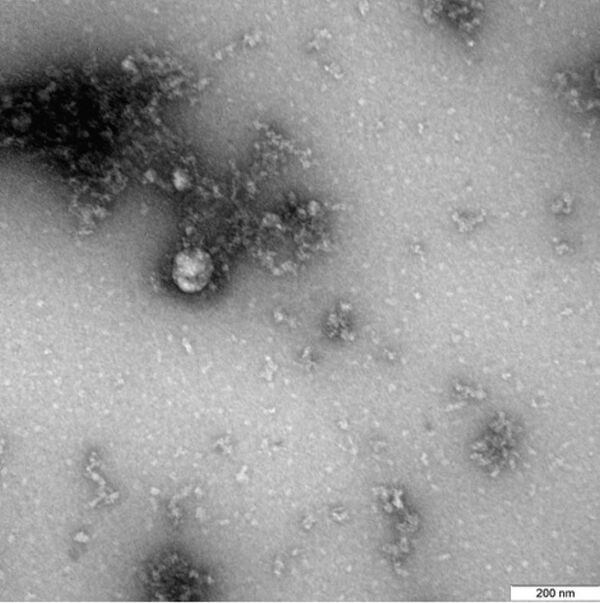

В России показали первый в мире снимок британского штамма COVID-19

15:29 25.01.2021 (обновлено: 14:05 10.03.2021) Фотография вируса под микроскопом получена в рамках продолжающегося изучения свойств данного варианта нового коронавируса.

"Данный снимок британского штамма коронавируса был выделен от пациента в декабре 2020 года", - говорится в публикации.

Фотография вируса под микроскопом получена в рамках продолжающегося изучения свойств данного варианта нового коронавируса, включая его структурные особенности и проявления в клеточных культурах и экспериментальных моделях с использованием лабораторных животных.